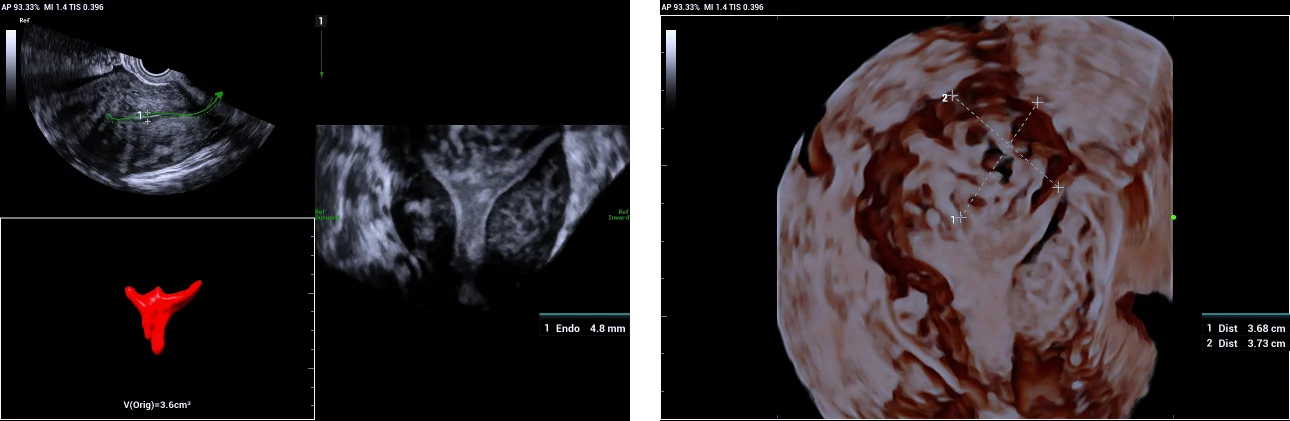

5. Sub-mucosal fibroid indenting the fundal endometrium.

Use of Smart ERA in diagnosis of Mullerian duct abnormalities - Sub-mucosal fibroid indenting the fundal endometrium

Smooth indentation of fundal endometrium giving a similar appearance to arcuate uterus.